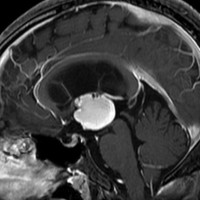

5歳の時に発見され23歳まで18年間経過観察をされてきた患者さんです。腫瘍はゆっくり,しかし確実に増大して,手術前には頭痛がひどく薬も効かず歩けなくなったという症状でした。術後に頭痛が無くなったので,のう胞による症状だったのでしょう。

下垂体柄の周囲にのう胞性腫瘍があります。T1強調画像では等信号,T2強調画像ではまだらな信号になっています。23年という長い経過から液状内容物が固形化したものと推定されます。T2で低信号となる部分があるのですが,黄色肉芽腫とは異なる像です。

下垂体柄は長く伸びています。のう胞による長期の圧迫のため斜台上部がerosionになって凹んでいます。トルコ鞍内の中間葉の位置に典型的な小さなラトケのう胞(黄色矢印)がみられますが,これは長年変化していませんでした。

左前頭側頭開頭 pterional approachで,のう胞壁を含めて完全摘出 complete removalしました。のう胞は下垂体柄の左側に付着してそこから発生したものでした。内容物は固体で寒天状のコロイドでした,一部軟らかくて一部は線維化していました。のう胞壁は半透明で薄い部分も線維性の膜状の部分もありました。病理検査では上皮細胞が証明されて内胚葉のう胞 endodermal cystの診断です。

ラトケのう胞はhiatusから内容液吸引だけして,皮膜はもちろんそのままにしています。